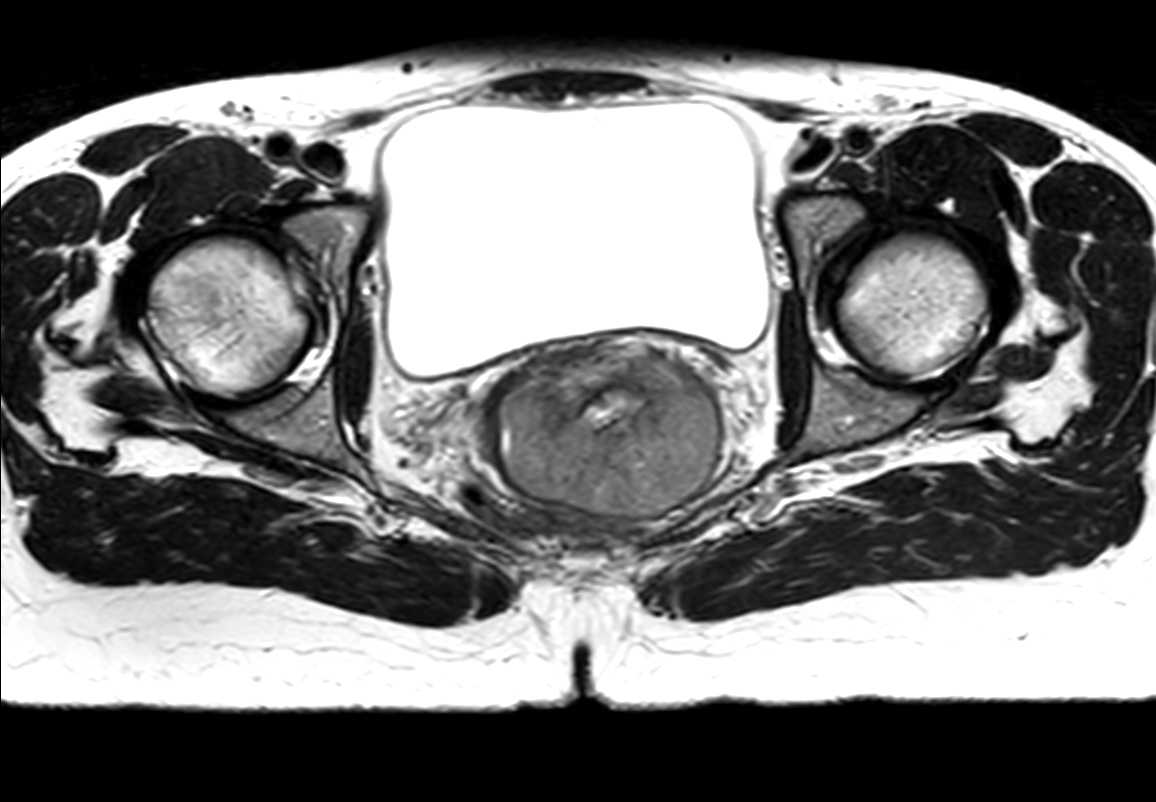

Patient diagnosed with cervical cancer referred for external beam radiotherapy. Three MRIs with different bladder filling were acquired: Half full (mid), empty and full bladder. Patient was imaged at Ingenia MR-RT 1.5T using FlexCoverage Anterior Coil in combination with the integrated Posterior Coil.

Axial T2w TSE mid

-